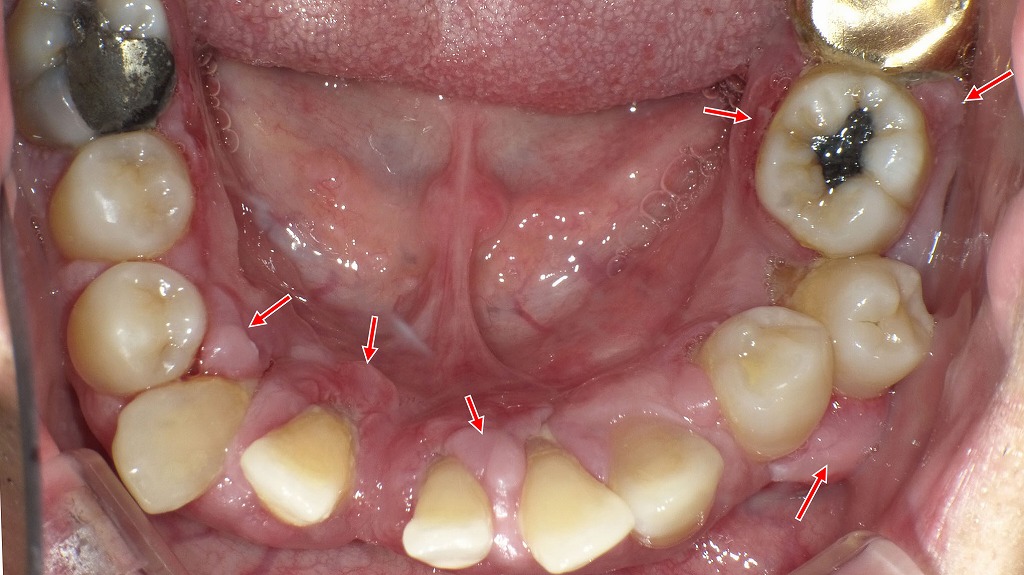

— 根尖病巣などの慢性炎症がある場合の注意点 —

赤矢印が示す部分には大きな根尖病巣(慢性炎症)が存在しています。

ビスフォスフォネート製剤(骨粗しょう症治療薬)を使用している方は、炎症のある歯や抜歯部位から顎骨壊死が起こるリスクが上昇します。

治療開始前には、歯科での精密検査と炎症源の除去が重要です。